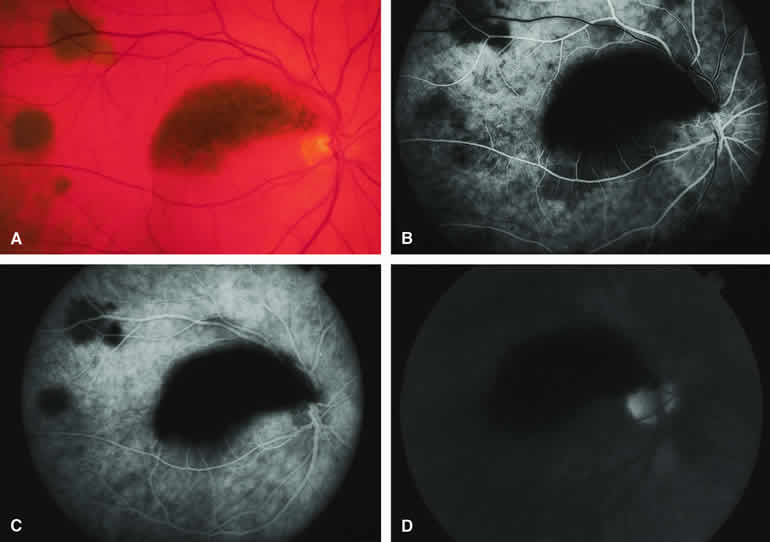

Typical Melanotic Choroidal Nevus

Fluorescein angiography of a typical choroidal nevus with bland surface features (see Fig. 1) shows the entire lesion to be hypofluorescent relative to the adjacent uninvolved choroid throughout the study. No large-caliber choroidal blood vessels are usually identifiable within the lesion. The retinal vasculature overlying the lesion appears well defined and normal on fluorescein angiography.

ICG angiography of a typical melanotic choroidal nevus (see Fig. 2) shows better definition of the basal area of the lesion than does fluorescein angiography. The entire lesion appears completely and uniformly dark throughout the ICG angiogram. Only the larger retinal blood vessels overlying the nevus are usually demonstrated on ICG angiography.